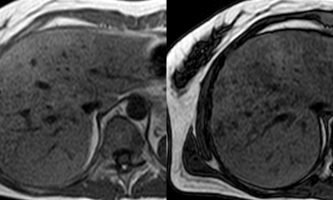

El estudio se complemento con resonancia magnética, donde se demostró la presencia de múltiples imágenes focales hepáticas confluentes con disminución de la señal en secuencias fuera de fase, no mostrando alteración de la señal en secuencias potenciadas en T2, sin signos de restricción al pulso difusión ni refuerzos anómalos luego de la administración de contraste endovenoso, estos hallazgos confirman la sospecha de esteatosis focal multinodular (fig. 5, 6 y 7).